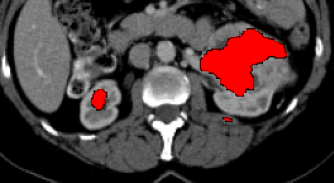

Current research on deep learning for medical image segmentation exposes their limitations in learning either global semantic information or local contextual information. To tackle these issues, a novel network named SegTransVAE is proposed in this paper. SegTransVAE is built upon encoder-decoder architecture, exploiting transformer with the variational autoencoder (VAE) branch to the network to reconstruct the input images jointly with segmentation. To the best of our knowledge, this is the first method combining the success of CNN, transformer, and VAE. Evaluation on various recently introduced datasets shows that SegTransVAE outperforms previous methods in Dice Score and $95\%$-Haudorff Distance while having comparable inference time to a simple CNN-based architecture network. The source code is available at: https://github.com/itruonghai/SegTransVAE.